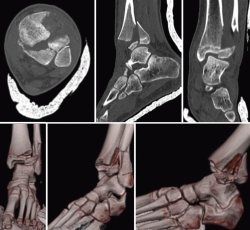

Se realizó una TC del tobillo que confirmó el diagnóstico de fractura triplanar en 3 fragmentos con fractura de peroné con ligero desplazamiento (Figura 2).

Figura 2. Tomografía computarizada + reconstrucción 3D: signo de Mercedes-Benz. Fractura Salter-Harris de tipo III en anteroposterior y de tipo II en proyección sagital + fractura de peroné.